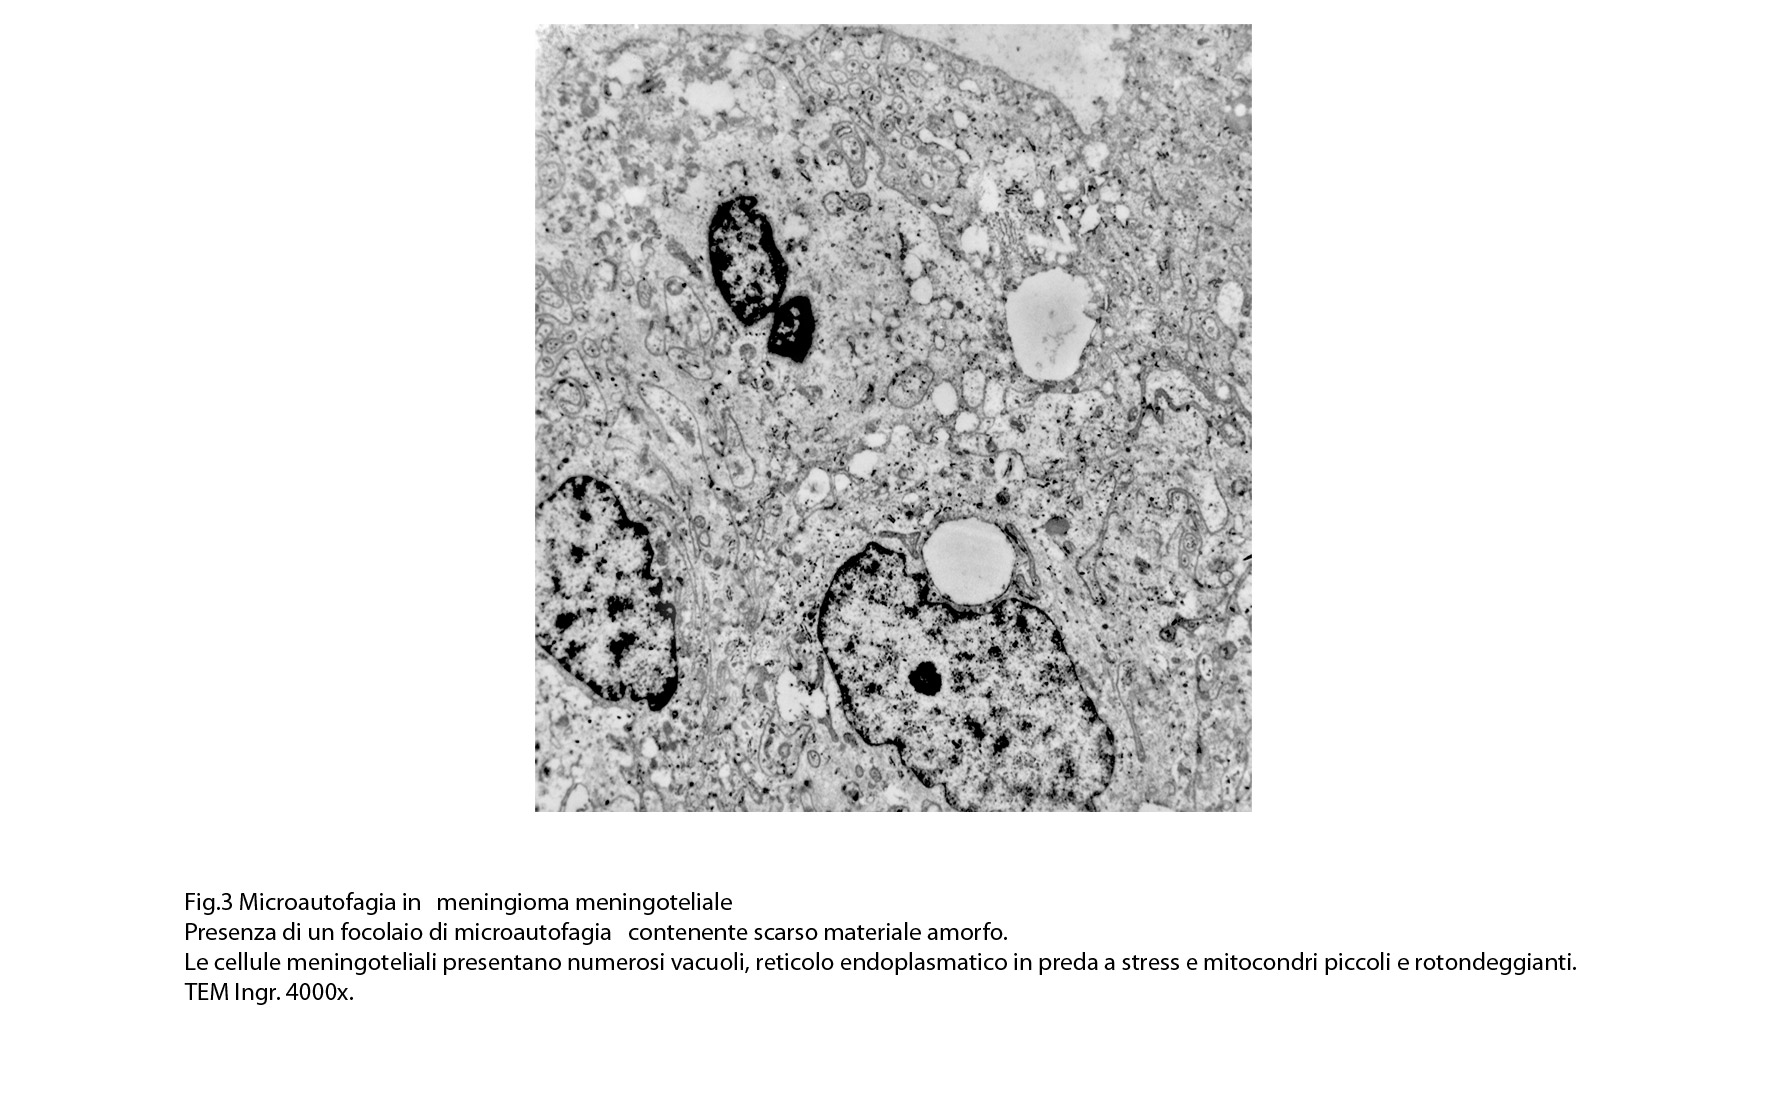

1) MICROAUTOFAGIA

Nel citosol si repertano vescicole di piccole dimensioni delimitate da una membrana di contorno a mono strato. Il loro lume è occupato da materiale amorfo e da corti filamenti distribuiti in modo disordinato.

Queste vescicole sono distribuite in modo irregolare, anzi casuale e si ritrovano ad essere isolate o riunite in piccoli aggregati formando un’immagine definita corpi multivescicolari.

Frequentemente questi focolai si ritrovano commisti ad altri aventi i caratteri della macroautofagia e sono in parte da questi mascherati. A parte questi particolari reperti,il citosol è occupato da numerosi mitocondri di piccole dimensioni e di forma rotondeggiante e di aspetto compatto,da ergastoplasma rugoso e da quote ben rappresentate di reticolo endoplasmico e di strutture lisosomiali.